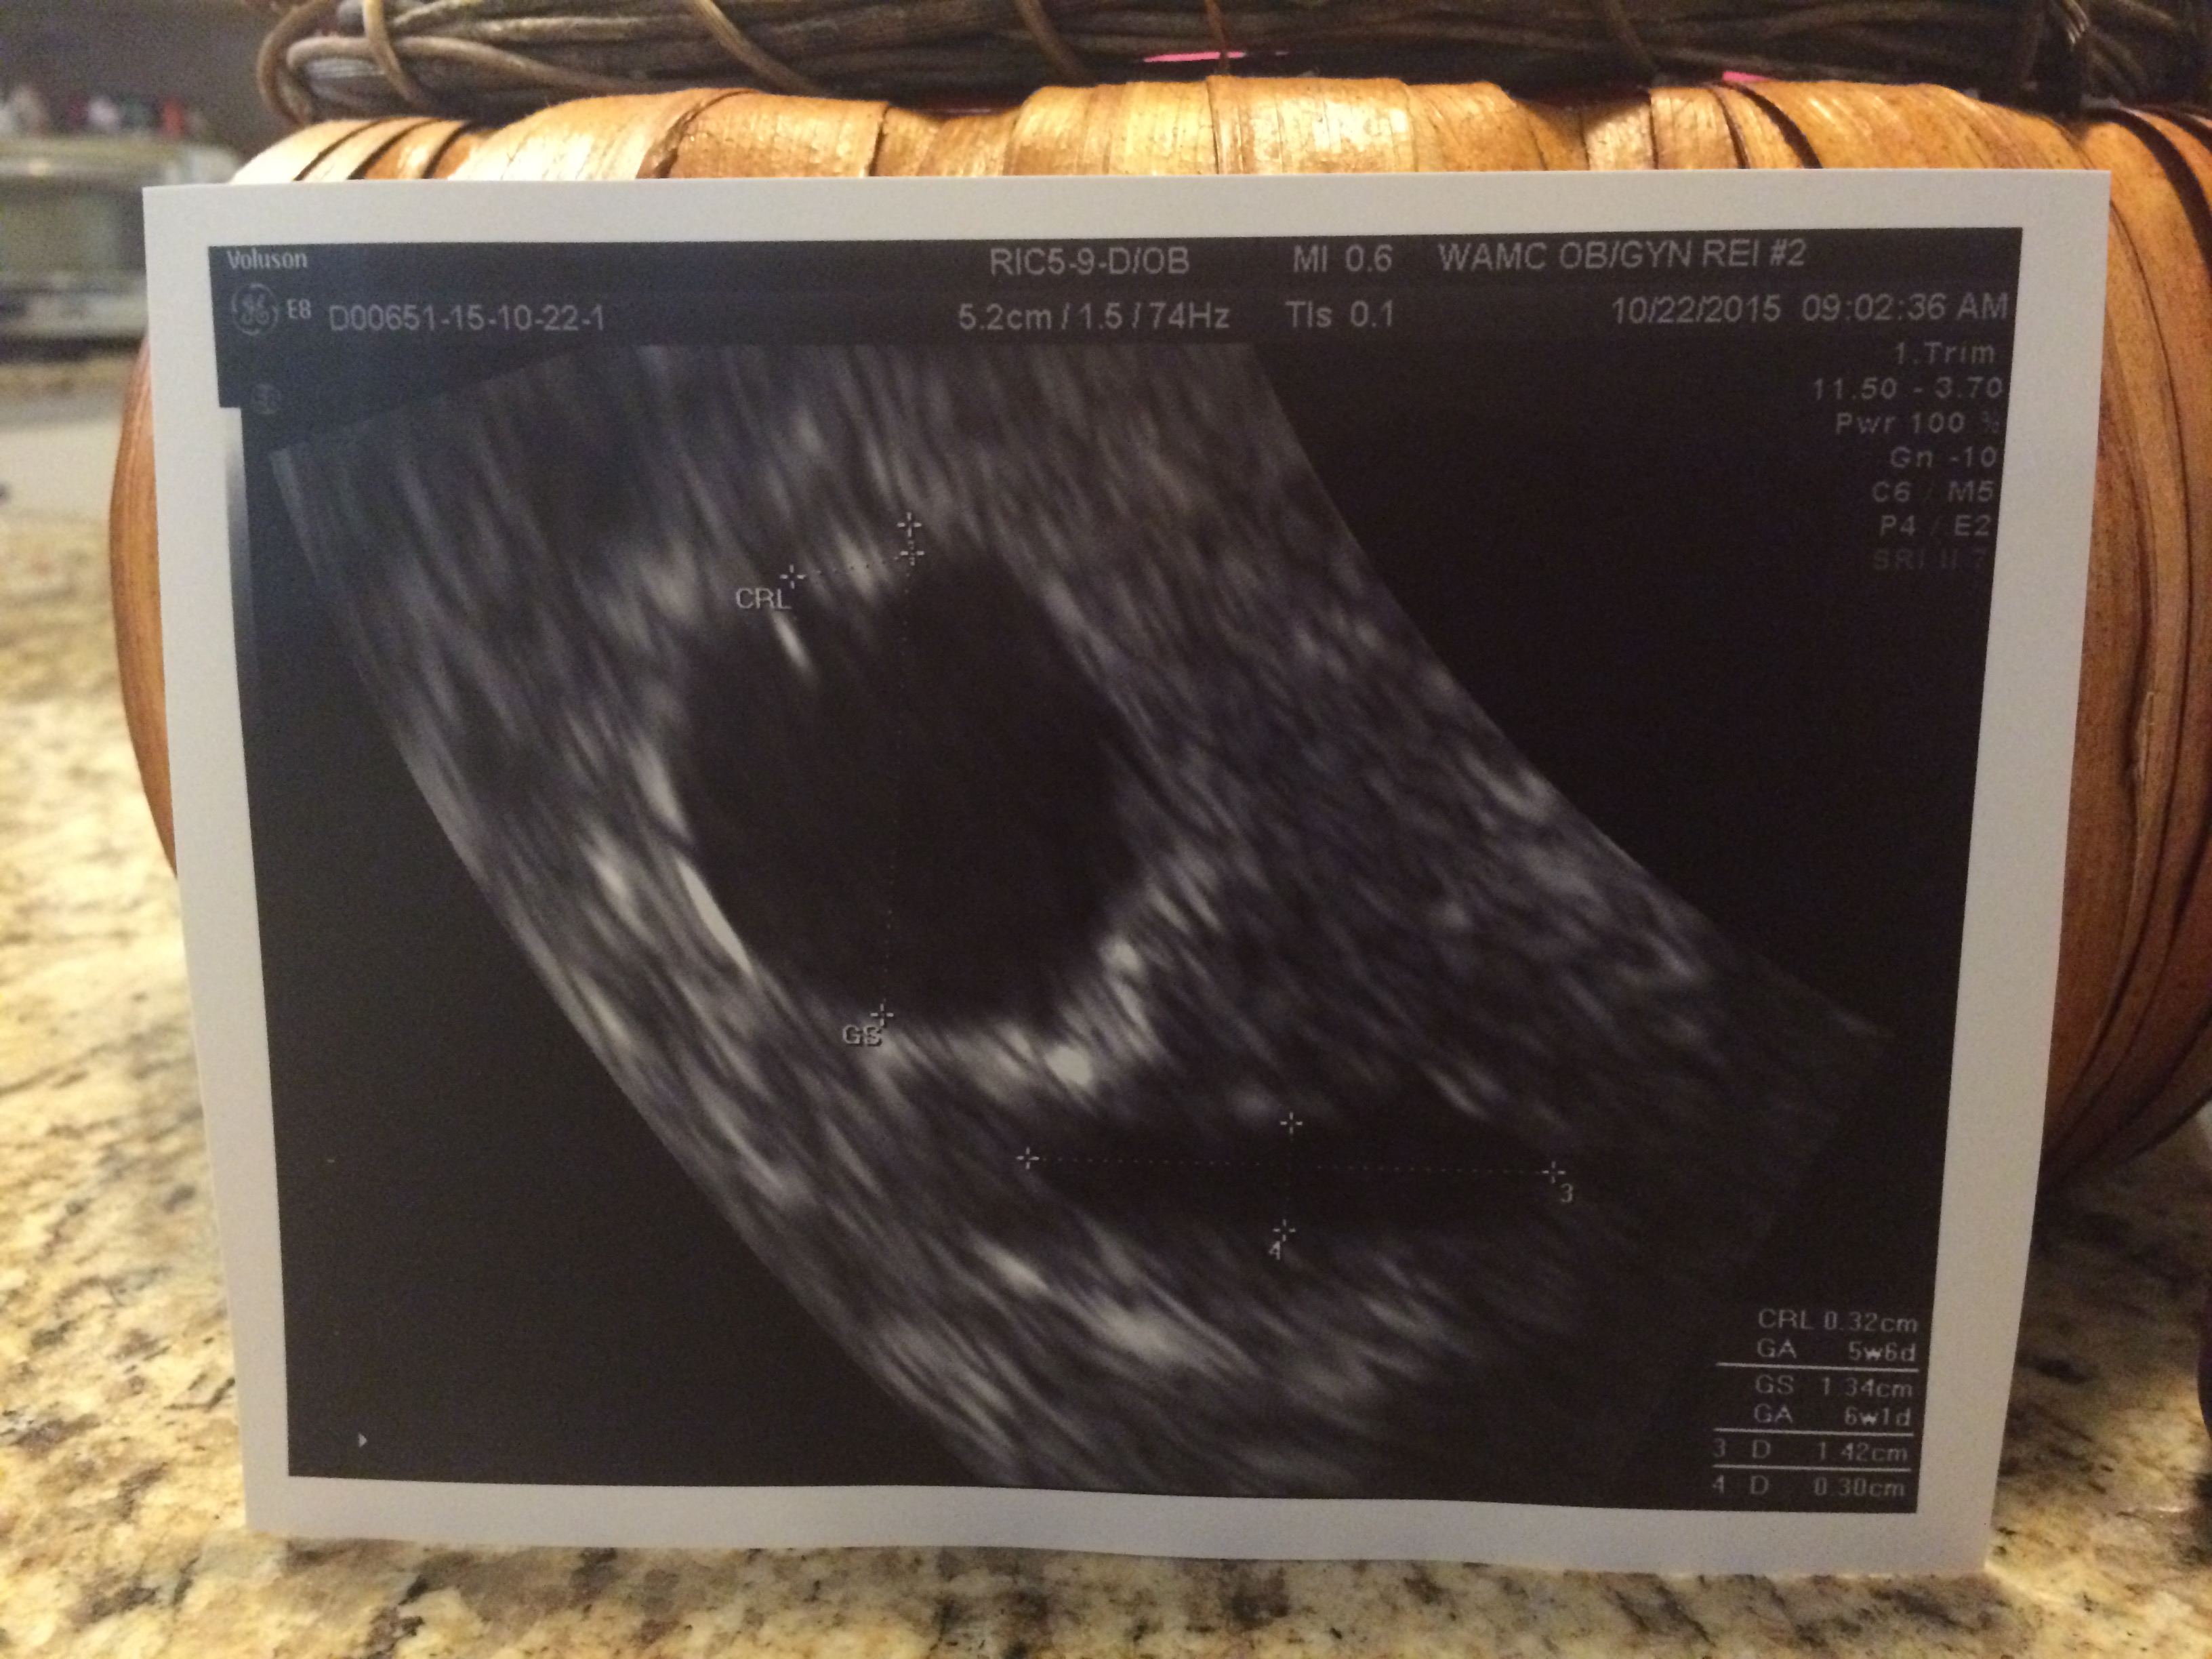

Hi ladies! This morning I went in for my 6 weeks u/s. We have a heartbeat and an appropriately sized GS! So thankful! However, they mentioned seeing some fluid in my uterus. They said they can't be certain if its blood or another type of fluid, but that they will be keeping an eye on it. Has anyone else been told this? Of course they told me not to worry and that in many cases this fluid can be reabsorbed as the baby grows. Not worrying seems impossible though! I was also given progesterone suppositories to help things along 'chemically'. I should mention that I'm being seen by an infertility specialist so I'm not sure if any of this would be considered 'nothing to worry over' had I not had multiple miscarriages and great difficulty TTC. So far, I've not had any bleeding/spotting/unusual cramping so I'm trying to remain hopeful... Plus, those early signs of pregnancy are in full swing! I have had a little bit of a watery clear discharge (TMI, I know) but didn't think anything of it since I've read that could be completely normal. Anyway, any advice would help! I wish all of you a blessed pregnancy!